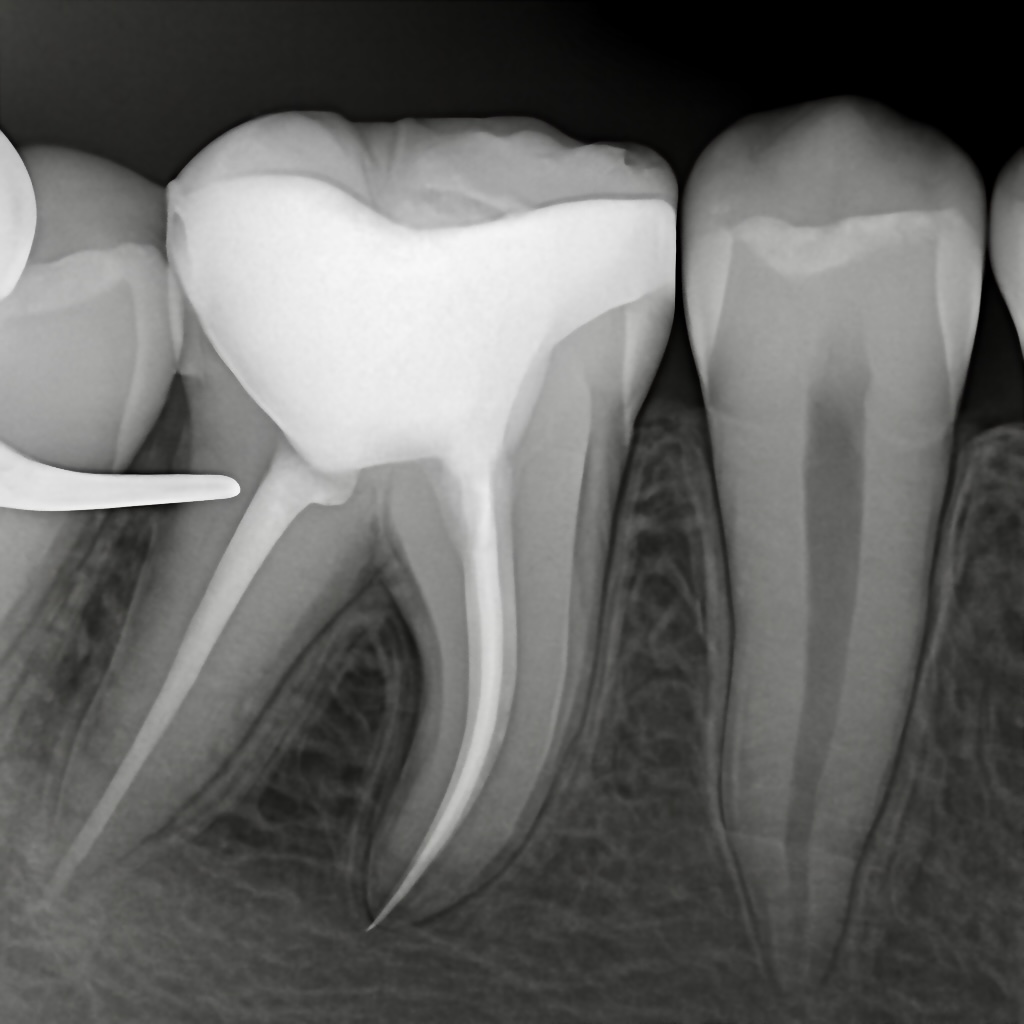

Radiographic

The periapical radiograph showed:

- Deep proximal decay approaching the pulp.

- Loss of dentin support under the marginal ridge.

- Widening of the periodontal ligament space.

- No vertical root fracture signs.

Post-obturation radiograph confirmed clean taper and ideal fill.

- Clean obturation

- Restored coronal seal

- Restoration margins well-adapted